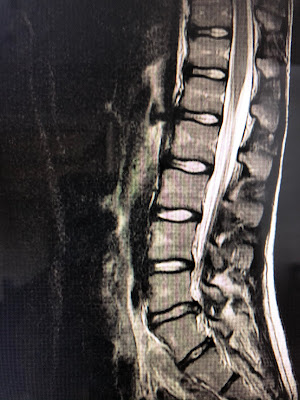

Well we finally received the answer as to why Zach has been limping after every single soccer game since April. Drum Roll Please...after his first ever MRI the results came back that he has one major bulged disc and a couple other minor bulges that are pinching a nerve! Ouch! So much for thinking it was a growth spurt issue or sore muscles. Ugh! I feel so horrible it took us this long to figure it out. And the exact incident that caused it all is still up for debate. I think it might have been him lifting weights at Sunset with the other eighth grade boys, but he can't remember doing a single move that might have triggered this type of damage. So we work backwards through all the games he has been playing and rack our brains trying to remember a fall or a hit that might have happened, but still nothing significant comes to mind. So finishing out his freshman year soccer season is no longer an option and we are all bummed for him, and hoping for the quickest recovery possible.